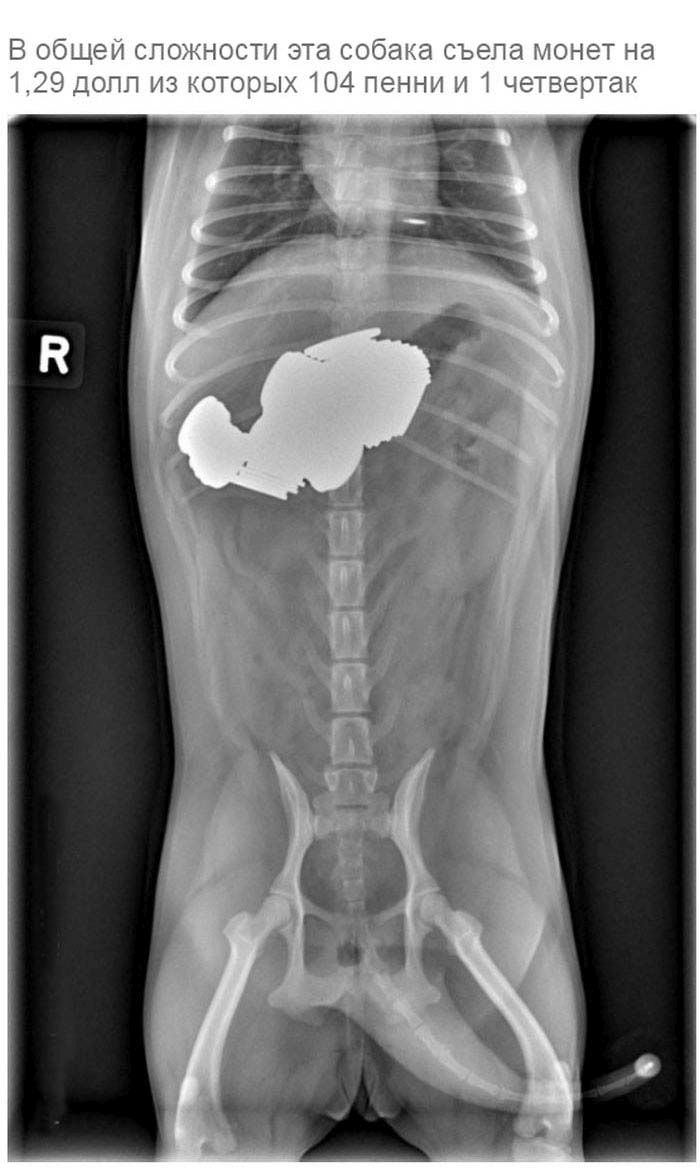

» Что может оказаться в желудке собаки

Что может оказаться в желудке собаки